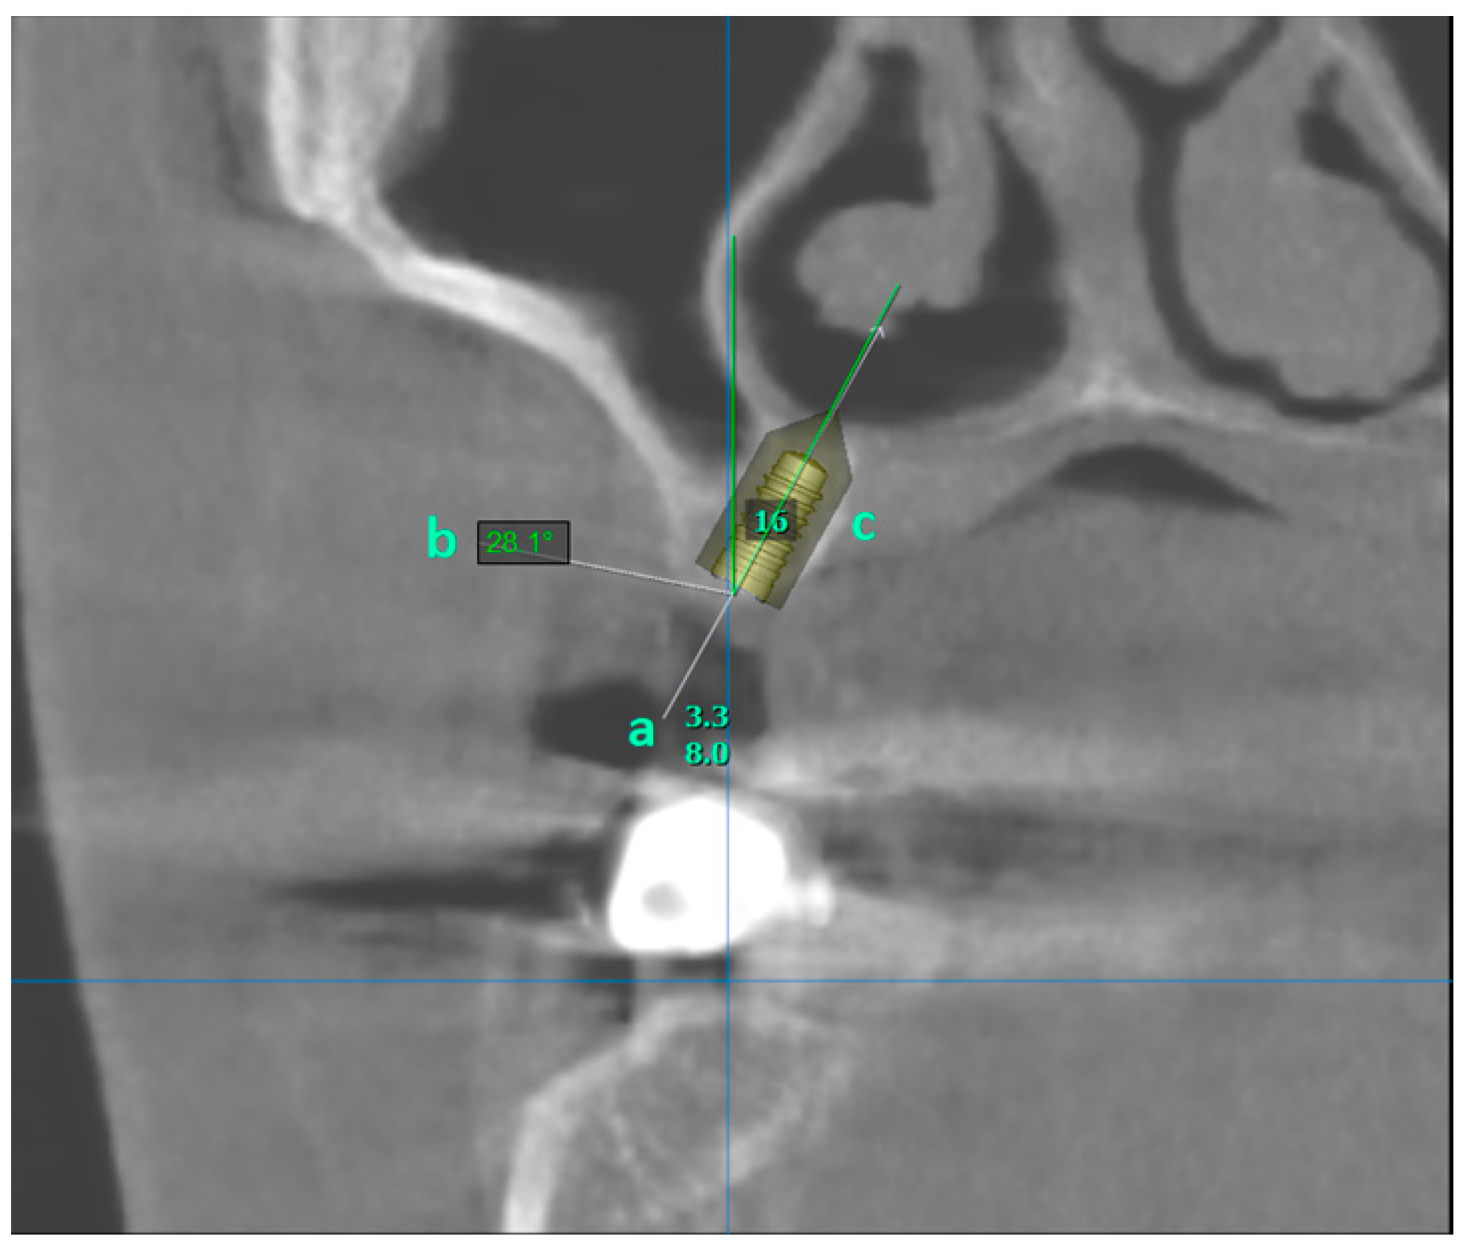

Avoiding Sinus Floor Elevation by Placing a Palatally Angled Implant: A Morphological Study Using Cross-Sectional Analysis Determined by CBCT

2. Materials and Methods